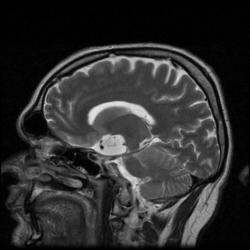

Женщина 47 лет, в течении долгого времени страдала от головных болей. В последние несколько месяцев - прогрессирующая потеря зрения (на оба глаза).

Случай "учебный", и сложностей не должен представлять.

Presented images are corresponded for cerebral (right temporal-occipital region) neoplasia; high grade glioma is most suggested.

Глиальная опухоль.